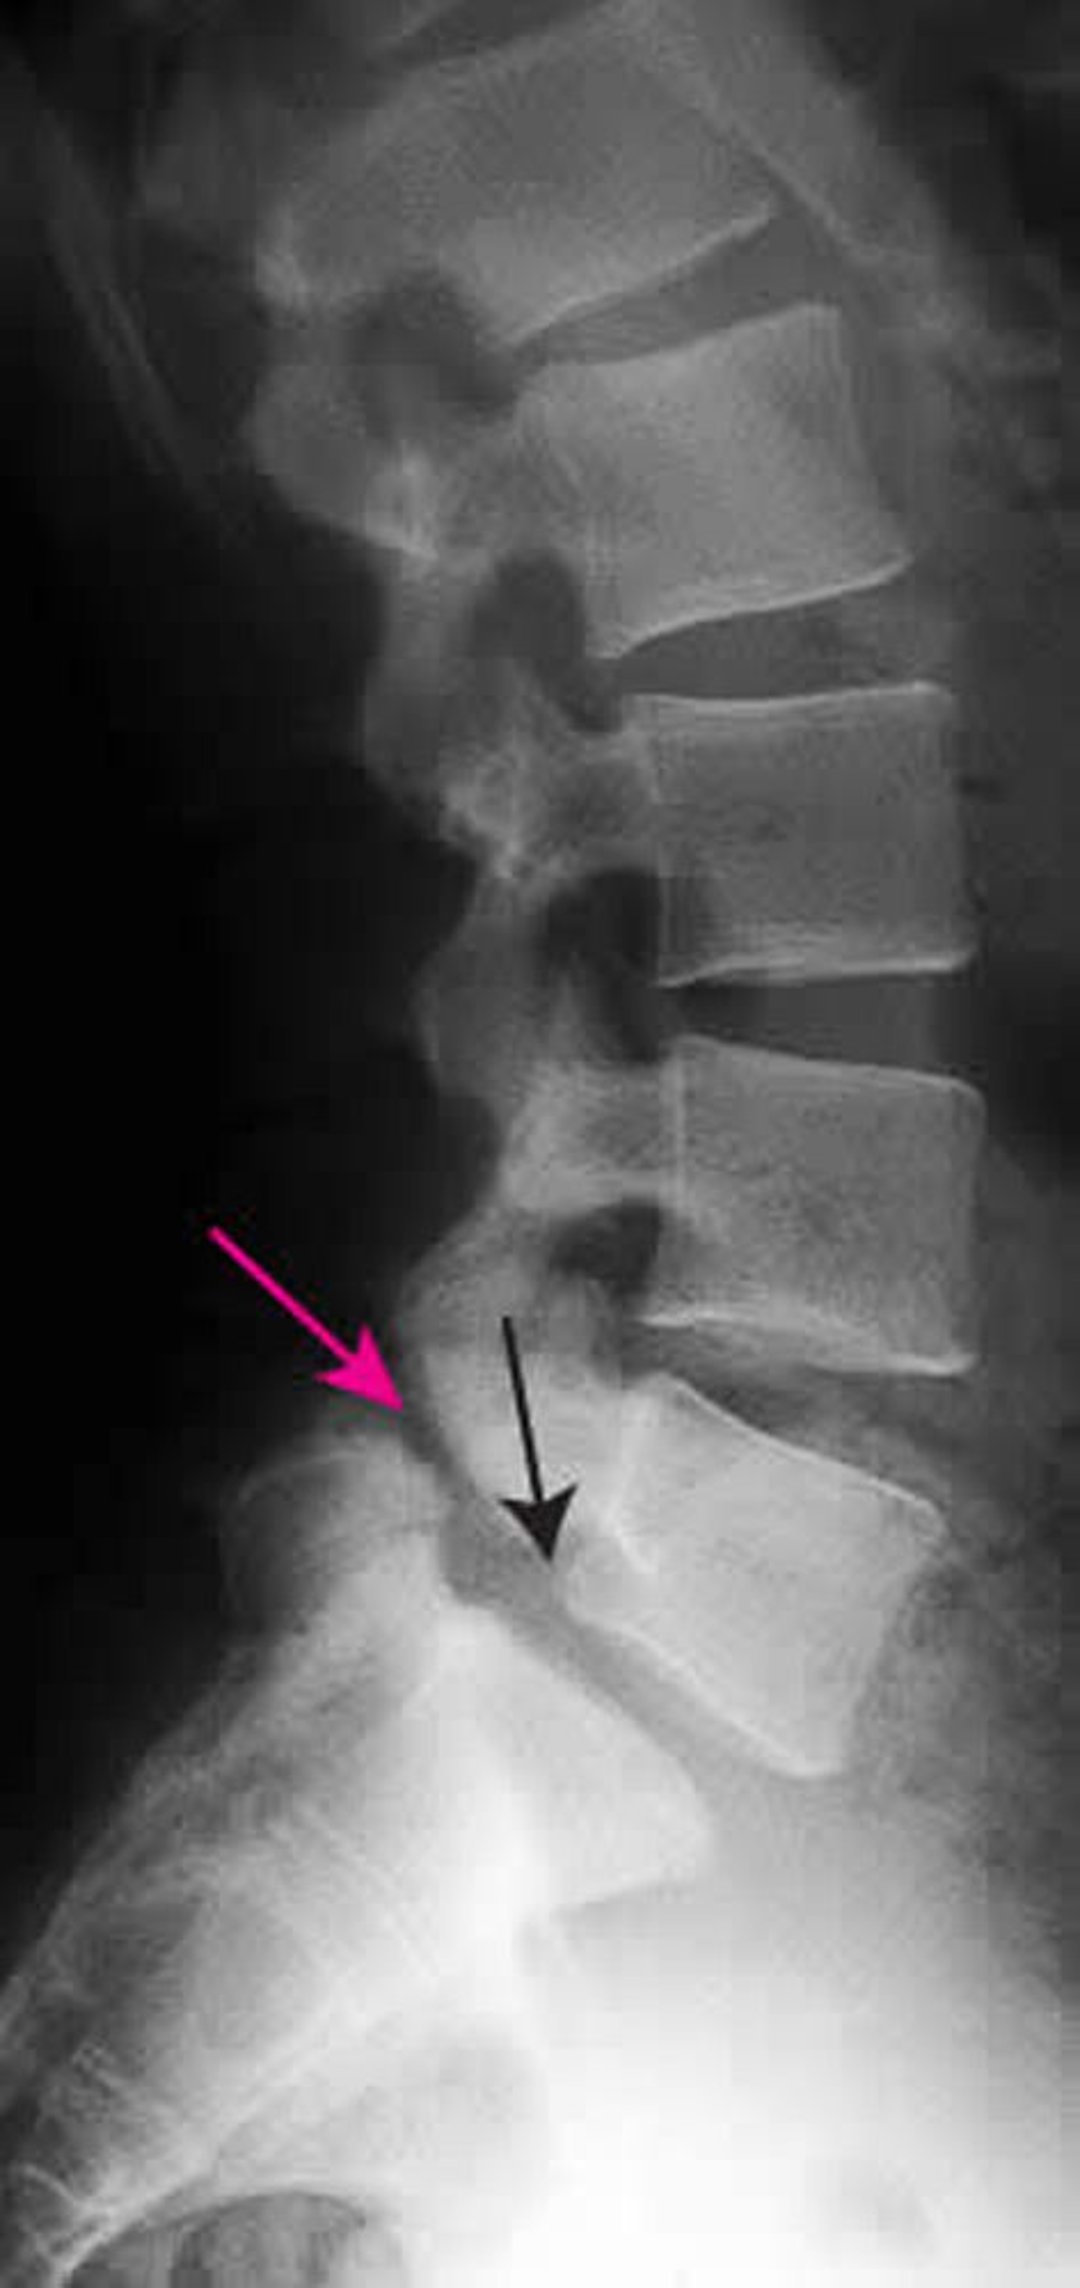

このX線写真では,L5-S1のgrade Iの脊椎すべり症が認められる。黒矢印はL5の後縁を示し,L5はS1に対し前方に亜脱臼している。赤矢印は,脊椎分離症(関節突起間部の欠損)を示している。